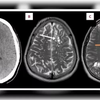

A sepse é uma resposta extrema do sistema imunológico a uma infecção, e pode levar à morte. Ele desenvolveu coágulos sanguíneos, pneumonia, falência de órgãos e síndrome do desconforto respiratório agudo (SDRA). A infecção bacteriana também atingiu seu coração, causando danos graves.